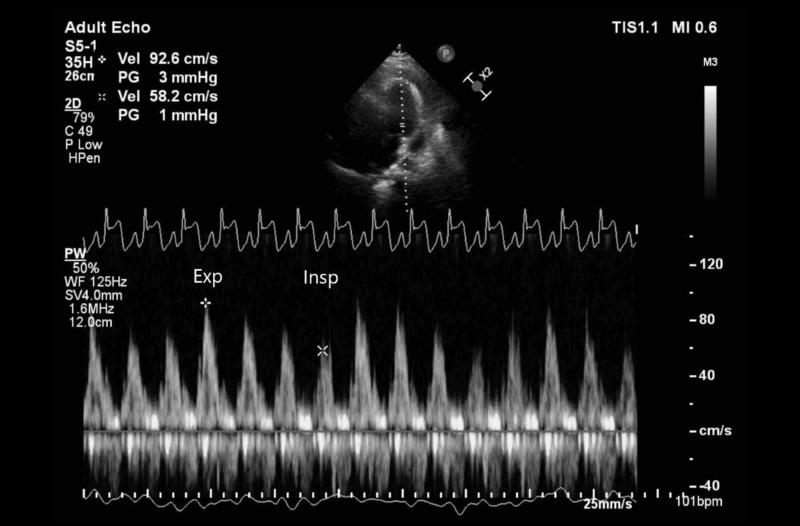

As the COVID-19 pandemic evolves, the medical community continues to discover novel clinical manifestations of the severe acute respiratory syndrome coronavirus 2 (SARS-CoV-2) virus. Often, extrapulmonary manifestations occur simultaneously with pulmonary disease. However, there is a paucity of literature describing the cardiac manifestations of COVID-19 in the absence of pulmonary findings. We report a rare case of acute pericarditis presenting with pericardial effusion and cardiac tamponade in a 43-year-old man diagnosed with COVID-19. This case emphasizes the importance of continued investigation regarding diagnosis and treatment of COVID-19 and its related symptoms.

随着新冠疫情的演变,医学界不断发现严重急性呼吸综合征冠状病毒2(SARS-CoV-2)的新临床表现。通常,肺外表现与肺部疾病同时出现。然而,在没有肺部表现的情况下,描述新冠病毒心脏表现的文献很少。我们报告了一例罕见病例,一名43岁确诊为新冠病毒感染的男性出现急性心包炎并伴有心包积液和心脏压塞。该病例强调了持续研究新冠病毒及其相关症状的诊断和治疗的重要性。